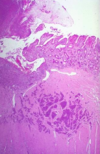

Normal Small Intestine

Normal Small Intestine